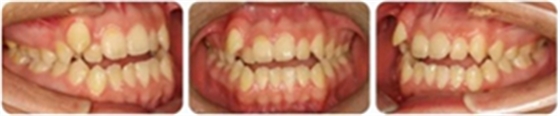

張某,男性,13歲,主訴前牙反頜伴開頜,要求矯治。

正面觀雙側(cè)基本對稱,垂直向基本協(xié)調(diào);側(cè)面觀直面型,下頜平面角較陡。顳下頜關(guān)節(jié)未見異常。

恒牙列,上中線右偏2mm,下中線左偏3mm,左側(cè)尖磨牙Ⅰ類 ,右側(cè)尖磨牙Ⅲ類。前牙反頜,13唇側(cè)低位萌出。上牙列擁擠度10mm,下牙列擁擠4mm。

(1)安氏Ⅲ類亞類錯合;

(2)前牙開頜、反頜;

(3)13唇側(cè)低位萌出。